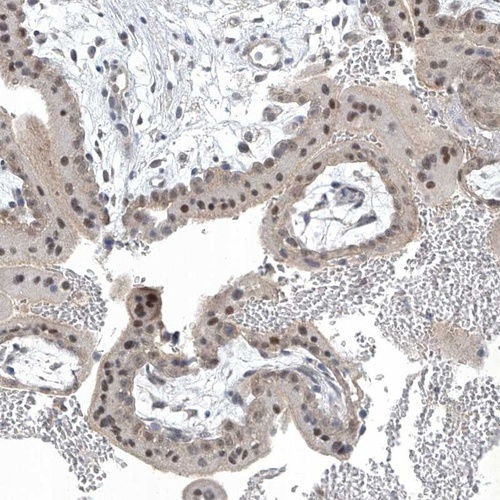

Immunohistochemical staining of human placenta shows distinct nuclear positivity in trophoblastic cells.